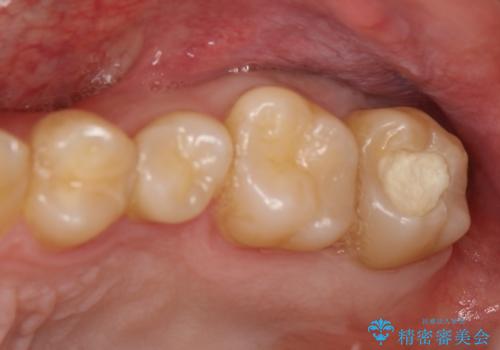

[フルジルコニアクラウン] 老朽化した銀歯を白く